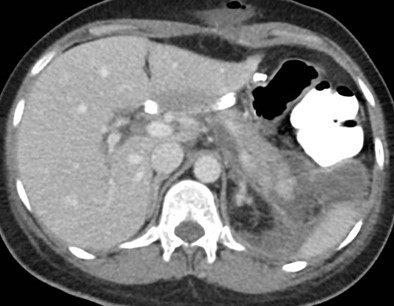

Caso 2

Paciente femenina de 48 años de edad que ingresa a Hospital Sanatorio Franchin por síntomas de cefalea y mareos, cuadro que se hace progresivo, presentando síncopes y posteriormente alteración del estado de conciencia. Los exámenes clínicos revelan una glucosa de 40 mg/dl, concomitante con insulina alta y péptido C elevado. Ingresa de forma programada para realización de duodeno pancreatectomía el 29 de mayo de 2021. Imágenes diagnósticas muestran estudio trifásico de tomografía de abdomen, lesión nodular en la cabeza del páncreas con ávido realce en fase arterial que en resonancia magnética se observa hiperintensa en T2, presenta restricción con la difusión y caída de la señal en el ADC. Además presenta realce tras la administración de contraste con gadolinio.

Estudio histopatológico reveló tumor neuroendocrino bien diferenciado grado 1.